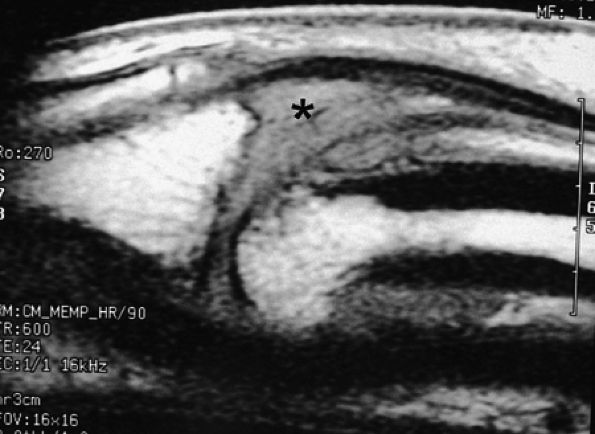

Axial and sagittal T1-weighted image or fat-suppressed proton density-weighted images may be sufficient to assess the tendon injury.43 However, when a short echo time (TE) is used, these sequences are subject to the magic angle phenomenon, which is most noticeable when the flexor or extensor tendon approaches an angle of 55 degrees with the B0 magnetic field. The magic angle phenomenon appears as increased intratendinous signal intensity that is present on all image planes and that decreases when TE values are lengthened.44 This artifact is relatively easy to recognize and typically occurs in areas such as the terminal band of the extensor tendon, the periarticular course of the flexor digitorum tendons, and the flexor pollicis longus in the thenar eminence (Fig. 11.23). In doubtful cases an additional T2-weighted sequence should be acquired.

FIGURE 11.23 ● Magic angle phenomenon. The flexor pollicis longus tendon (arrows) with high signal intensity with short TE sequences on all imaging planes, as seen on (A) a sagittal fat-suppressed T1-weighted image and (B) an axial T1-weighted image. (C) On images with long TEs or STIR images, the signal of the tendon becomes normal.